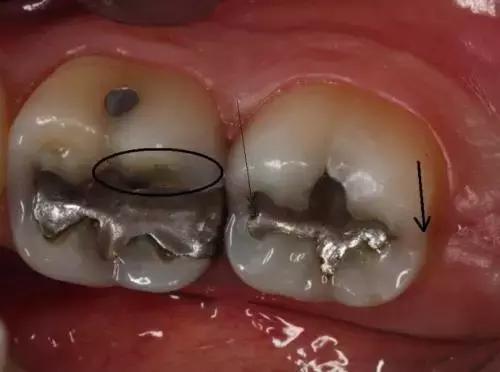

“*毒冰**牙”的症状

2.牙隐裂——*毒冰**会使服用者感到焦虑、亢奋或紧张,从而导致磨牙。你能看到他们的牙齿上有明显的磨耗痕迹。有时候就算是吃一些很软的食物(如土豆泥),也会使服用者的牙齿出现隐裂。

3.龋齿——*毒冰**成瘾者会因为口干反应而渴望吃含糖量高的食物和饮品。这样,口腔内靠糖类为生的细菌会大量繁殖,并分泌酸性物质,使牙齿损坏更严重。*毒冰**服用者的龋齿通常会从牙龈边缘发展到整个牙齿,前牙首当其冲。

4.牙周病——*毒冰**成瘾者通常不会定期做口腔检查,口腔保健的缺乏会引发牙周病。同时,牙齿和牙龈都需要血液来保持健康,*毒冰**使口腔组织的血管收缩,血流量减少,最终导致口腔组织坏死。

1.吸毒者龋齿发展到牙龈边缘以下。

2.吸毒者牙齿出现缺失。